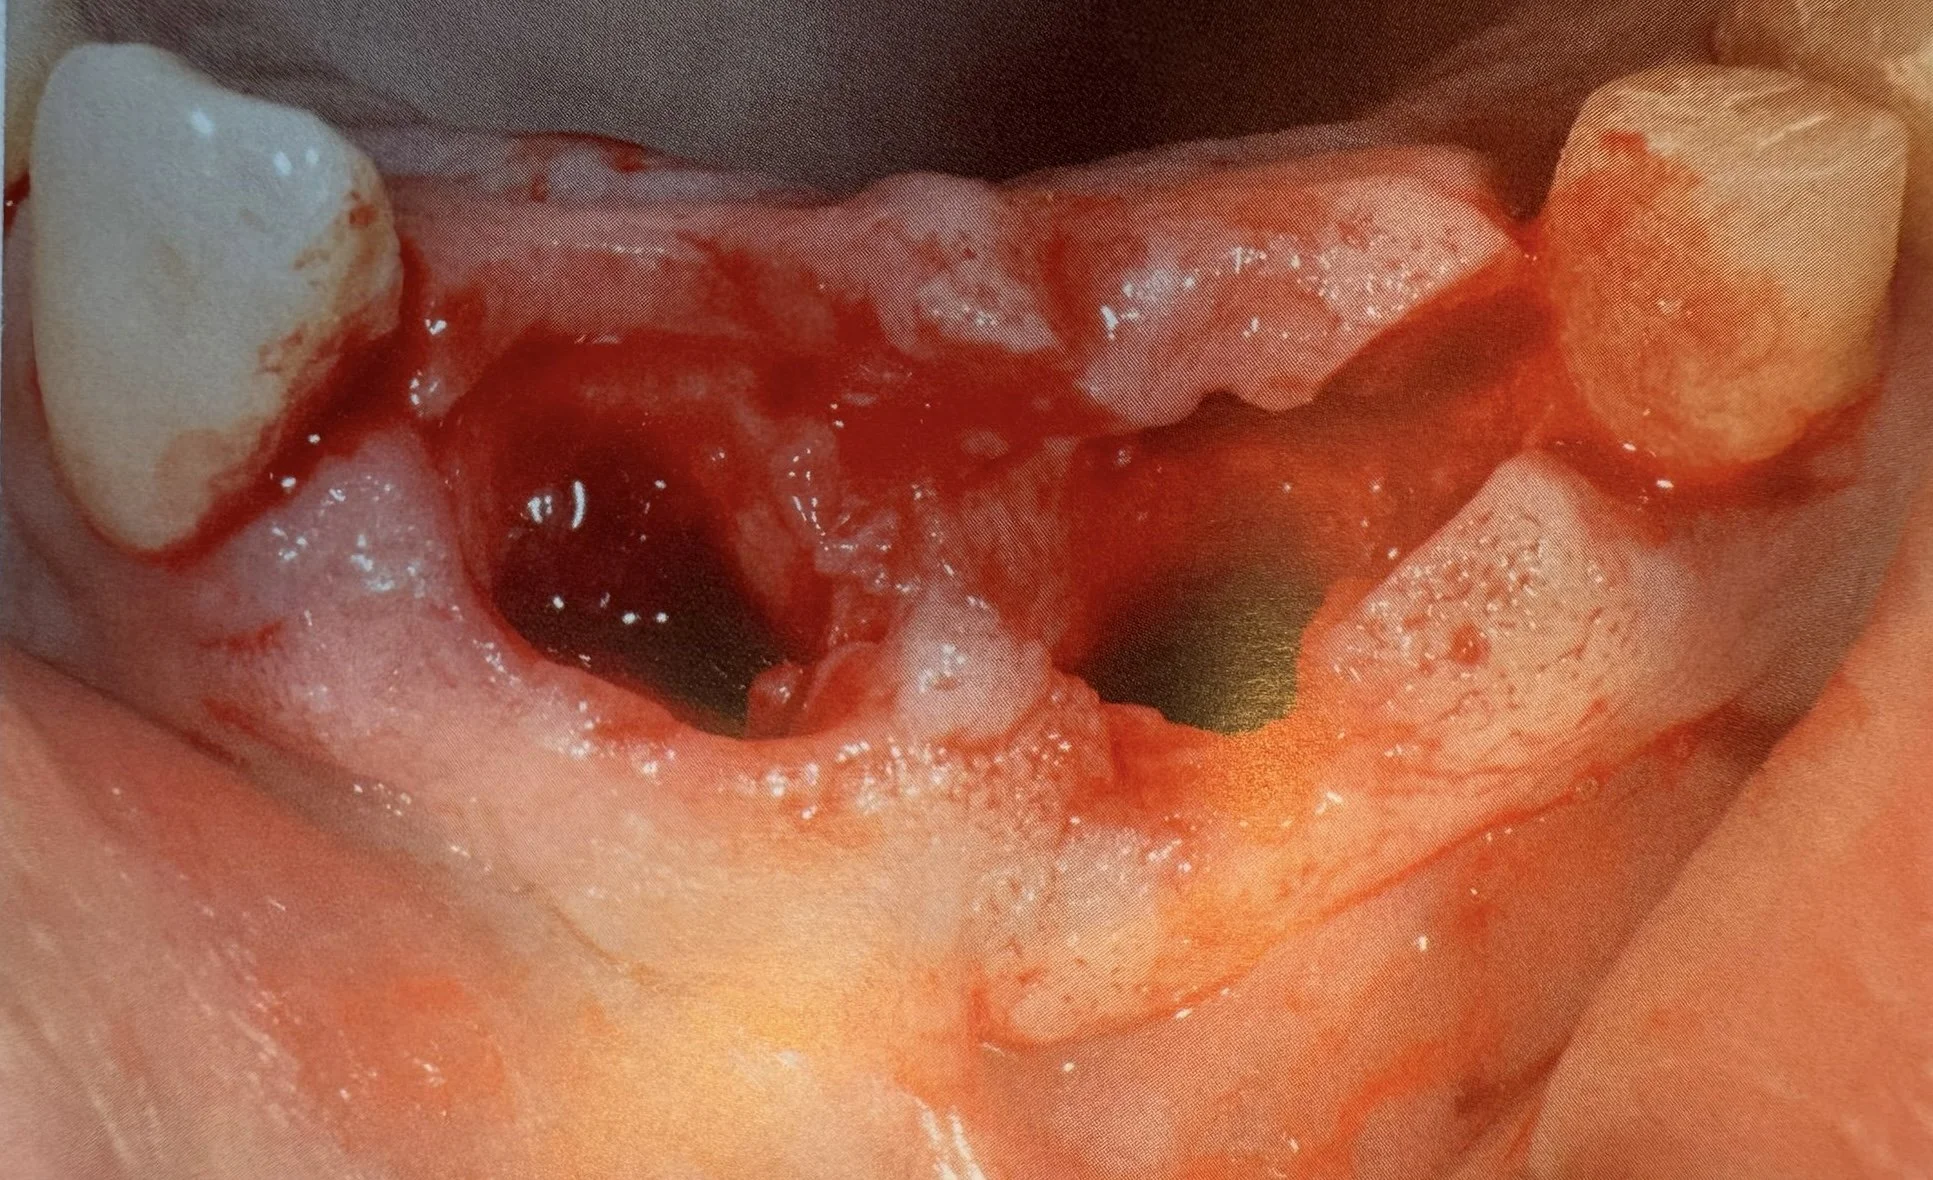

Estrazione, Rigenerazione Ossea e Riabilitazione Implantare

Riabilitazione post estrazione con impianto